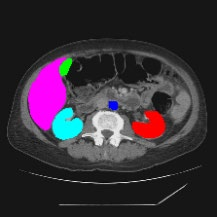

Transformers have made remarkable progress towards modeling long-range dependencies within the medical image analysis domain. However, current transformer-based models suffer from several disadvantages: (1) existing methods fail to capture the important features of the images due to the naive tokenization scheme; (2) the models suffer from information loss because they only consider single-scale feature representations; and (3) the segmentation label maps generated by the models are not accurate enough without considering rich semantic contexts and anatomical textures. In this work, we present CASTformer, a novel type of generative adversarial transformers, for 2D medical image segmentation. First, we take advantage of the pyramid structure to construct multi-scale representations and handle multi-scale variations. We then design a novel class-aware transformer module to better learn the discriminative regions of objects with semantic structures. Lastly, we utilize an adversarial training strategy that boosts segmentation accuracy and correspondingly allows a transformer-based discriminator to capture high-level semantically correlated contents and low-level anatomical features. Our experiments demonstrate that CASTformer dramatically outperforms previous state-of-the-art transformer-based approaches on three benchmarks, obtaining 2.54%-5.88% absolute improvements in Dice over previous models. Further qualitative experiments provide a more detailed picture of the model's inner workings, shed light on the challenges in improved transparency, and demonstrate that transfer learning can greatly improve performance and reduce the size of medical image datasets in training, making CASTformer a strong starting point for downstream medical image analysis tasks.